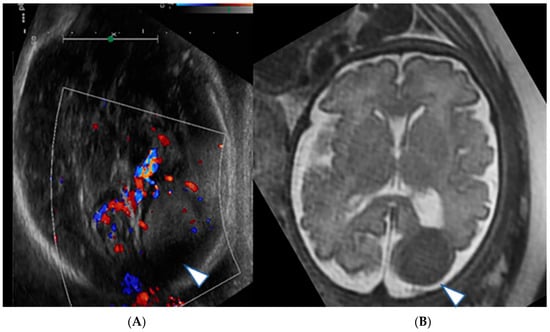

2. Case Series